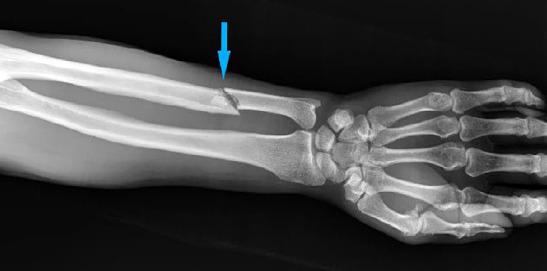

In the study, 1225 patients were evaluated, and 98.7% of them were women (mean age 35 [IQR: 17] years). Of the pa-tients, 63.1% were high school and university graduates. The rate of married women was 74.6%. No relationship was found between gender, age, educational status, and marital status (p>0.05). Most of the traumas were minor (85.4%) and blunt (81.9%) trauma, and the most common types of trauma were kicking (49.9%) and punching (47.3%). It was found that the most frequently affected areas of the patients were the head and neck (76.7%), and the frequency of pelvic trauma was high in male patients (p<0.05). The most com-mon bone fracture was nasal (40.5%) followed by ulna fractures (14.5%). The left-sided diaphyseal fractures were the most common in patients exposed to IPV. In our study, the frequency of mortality was 12.9%, and it was found to be significantly higher in males (p<0.05).

本研究共评估了 1225 名患者,其中 98.7%为女性(平均年龄 35 [IQR:17] 岁)。患者中 63.1%为高中和大学毕业生。已婚女性的比例为 74.6%。性别、年龄、教育程度和婚姻状况之间无相关性(p>0.05)。大多数创伤为轻微(85.4%)和钝性(81.9%)创伤,最常见的创伤类型为踢打(49.9%)和拳打(47.3%)。发现患者最常受影响的部位是头部和颈部(76.7%),男性骨盆创伤发生率较高(p<0.05)。最常见的骨折是鼻骨(40.5%),其次是尺骨骨折(14.5%)。在 IPV 暴露的患者中,左侧骨干骨折最为常见。在本研究中,死亡率为 12.9%,男性死亡率明显较高(p<0.05)。